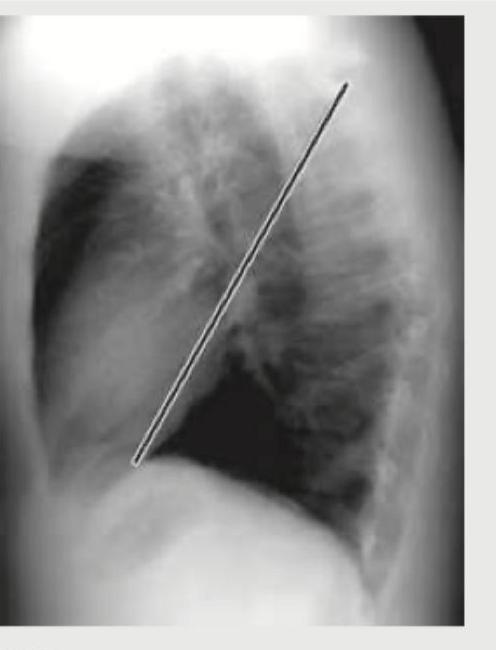

The lateral view chest X-ray shows:

Explanation: ***Major fissure*** - The image clearly shows an oblique line running from the mid-thoracic region superiorly and posteriorly to the diaphragm anteriorly, which is characteristic of the **major (oblique) fissure** on a lateral chest X-ray. - This fissure separates the **upper and middle lobes from the lower lobe** in the right lung, and the upper lobe from the lower lobe in the left lung. *Minor fissure* - The minor (horizontal) fissure is typically seen as a **horizontal line** on the lateral view, running from the mid-axillary line to meet the major fissure anteriorly. - It is located between the **upper and middle lobes** of the right lung only and is not depicted by the annotated line. *Azygos fissure* - An azygos fissure is an **anatomical variant** caused by the atypical migration of the azygos vein during development, creating a deep fissure in the superior aspect of the **right upper lobe**. - It would appear as a curvilinear line forming a "tear-drop" shape and is not represented by the oblique line shown. *Transverse fissure* - "Transverse fissure" is another name for the **minor (horizontal) fissure**. - As described earlier, its appearance and location on a lateral chest X-ray are distinct from the oblique line indicated.